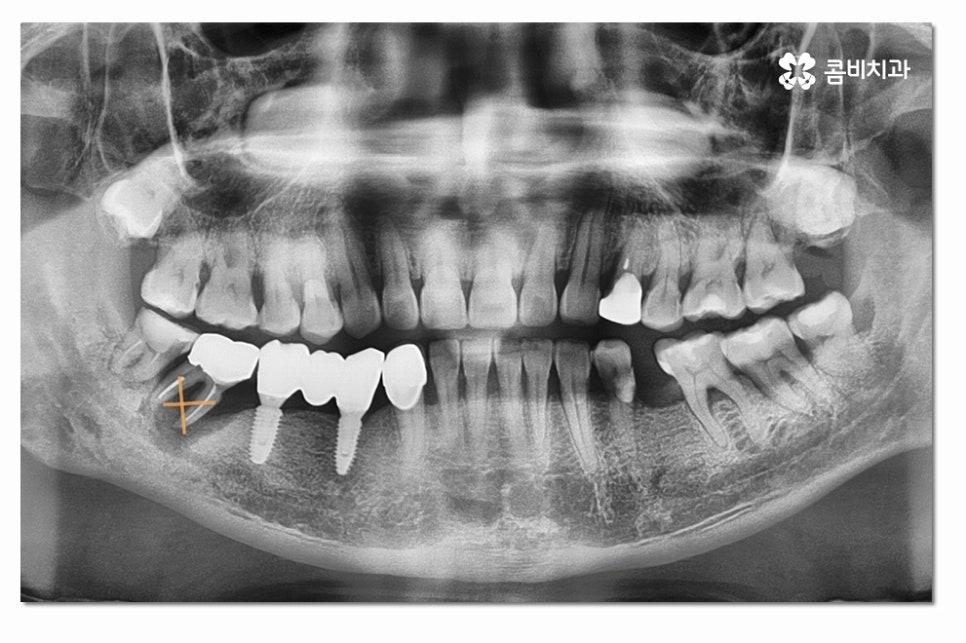

오늘 보여드릴 환자분은 어금니 임플란트 치료를 하게 된 사례로

일반적으로 어금니는 저작 기능을 중점적으로 수행하기 때문에

노화가 진행되면서 치아 사이에 틈이 생기고, 그 틈으로

음식물이 끼면서 치아와 잇몸 경계 부분에 치석이 쌓이기 쉬우며

사랑니로 인해 관리가 잘 안될 경우 충치나 염증으로

인해서 어금니가 손상될 수도 있어요.

위 사진처럼 어금니를 발치한 후에는 잇몸이 차오르길

기다리게 되고 임플란트를 식립할 잇몸 뼈가

충분한지 잇몸 상태를 정밀 검진을 통해 확인하는 과정을

거치며 잇몸이 부족한 경우에는 뼈이식을 받아야 할 수 있어요.

어금니임플란트의 경우 심미성보다는 기능성에 보다 집중된

치료가 이뤄지게 되는데 요즘은 3D CT 등을 통해

정확도 높은 진단이 이뤄지고 있지만 시술은 의사의 경험과

실력이 중요한 부분이기 때문에 어금니임플란트는

특히 저작기능을 수행하는 데 유리한 식립 각도와

위치 선정을 잘하는 것이 중요하다고 할 수 있어요.